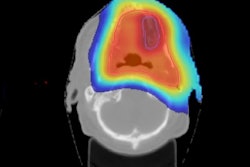

Bas Raaymakers, PhD, from UMC Utrecht in the Netherlands, considered the need for image guidance during radiation therapy. With advanced modalities such as IMRT allowing the sculpting of dose distribution, it becomes imperative that radiation is accurately delivered to the correct place. "Image guidance becomes more and more critical with these types of radiotherapy delivery," he explained.

Bas Raaymakers, PhD, from UMC Utrecht considers the need for image guidance during radiation therapy. Credit: James DaceyChanges in patient and tumor anatomy during a fractionated radiation course necessitate imaging between fractions to ensure the treatment remains accurate. "If you're going to deliver radiation 30 times, things are going to change," Raaymakers said. And even during treatment, motion due to breathing, for instance, can create uncertainties in dose delivery. Image guidance can help mitigate such uncertainties.

Raaymakers described the wide range of options available for guidance of external-beam radiotherapy. In-room CT-on-rails systems offer imaging prior to, though not during, treatment. Megavoltage imaging with treatment beam can be used before or during treatment and provides good bony anatomy visualization, albeit with low contrast and signal-to-noise ratio. Fluoroscopy systems also offer real-time guidance during irradiation.

Ultrasound can now be employed for treatment guidance, with Elekta's Clarity allowing inter- and intrafraction imaging, and other systems offering interfraction ultrasound guidance. Other approaches include radiofrequency tracking of implanted beacons and on-board cone-beam CT. Further ahead, biological guidance may be possible, enabled by the PET-guided system under development by RefleXion Medical.

Ultimately, MRI may prove the optimal guidance modality, offering real-time visualization of the tumor and its surroundings. As such, several groups worldwide are developing MRI-guided radiotherapy systems. The MRIdian from ViewRay, for example, which is based on three cobalt-60 sources and a 0.35-tesla MRI, was first used to treat a patient at the start of 2014 and is now in regular clinical use.